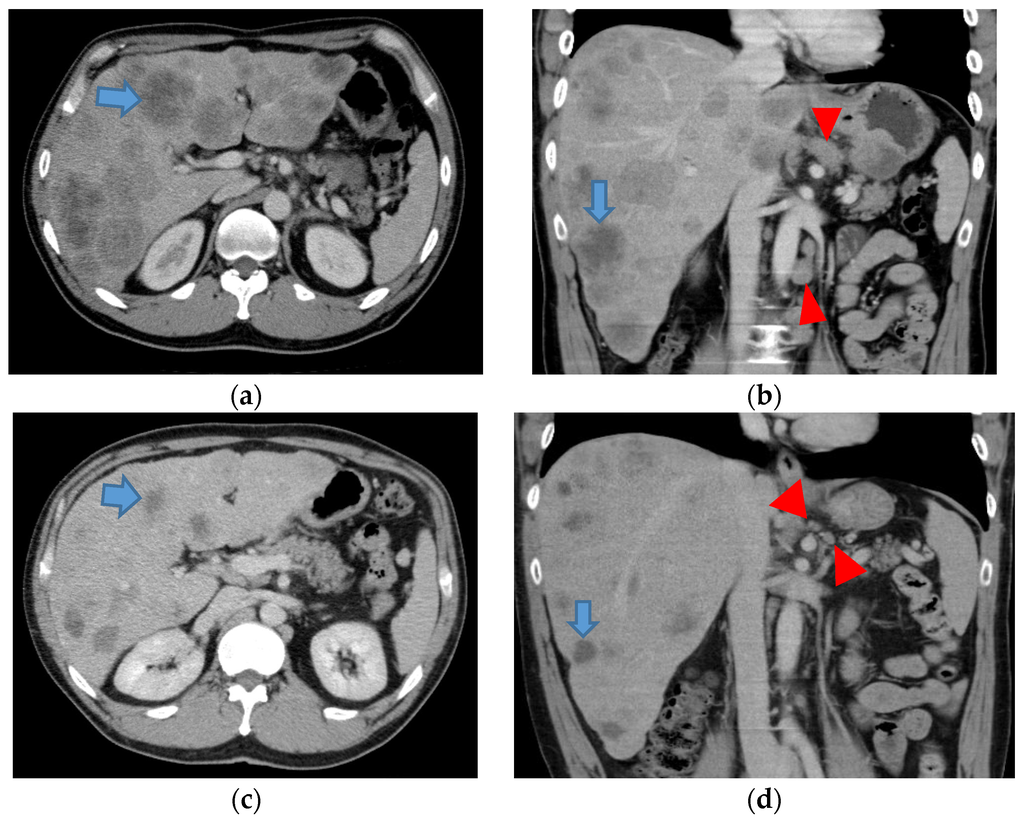

| 65 | Male | T4 N3 H3 | PSC plus lentinan | 33 | − |